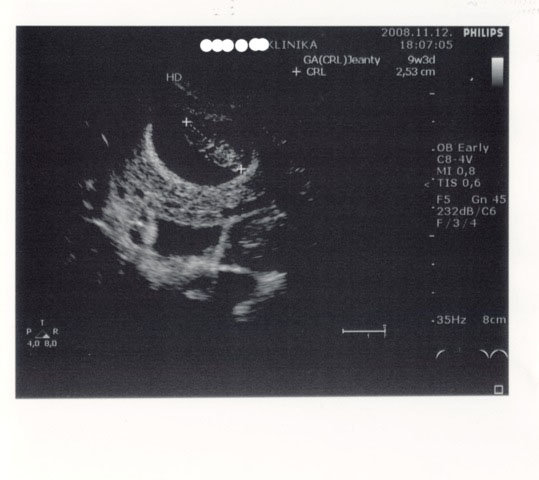

Ja, itt az ígért UH-s kép!de ebből eztán sokat nem láttok

Barátnőm észrevette, hogy 9 hetes vagyok rajta meg 3 napos! Végre annyi, amennyinek tudom, hogy lennie kell!! :lol: Kép